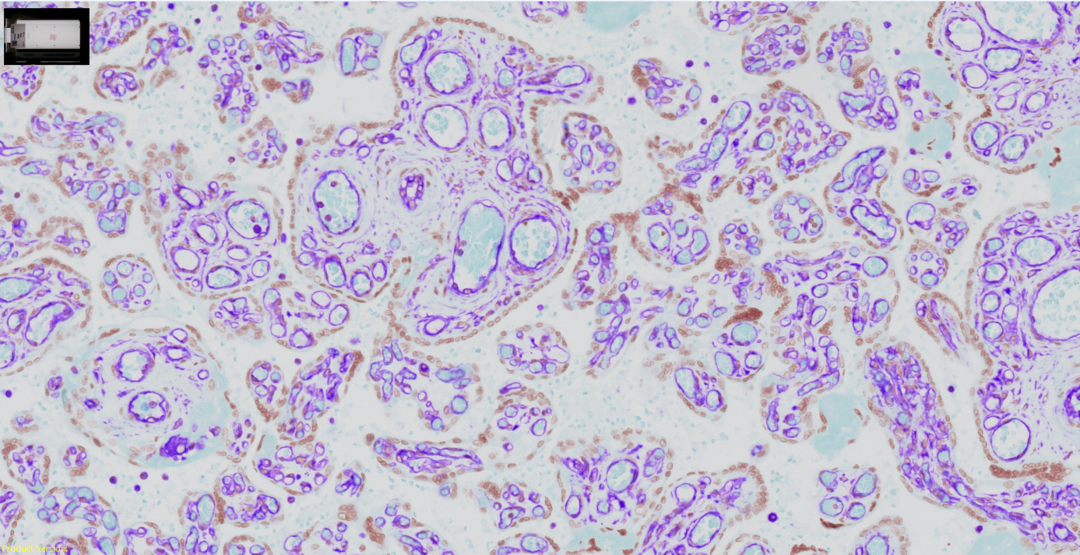

您多年來一直信賴的光學(xué)品質(zhì)如今已體現(xiàn)在專用玻片掃描系統(tǒng)中。基于病理學(xué)成像領(lǐng)域深厚的專業(yè)知識(shí)而打造,為組織學(xué)和細(xì)胞學(xué)樣品提供顯微鏡質(zhì)量的圖像。可驗(yàn)證的數(shù)字成像流程,系統(tǒng)化的色彩再現(xiàn)評(píng)估方法讓真實(shí)顏色準(zhǔn)確再現(xiàn)。

胎盤波形蛋白(Vimentin)的免疫組化染色(IHC)